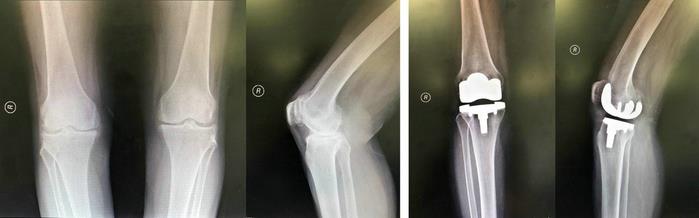

第四阶梯适用于关节磨损严重、上述治疗手段均无效的患者。在全身情况能耐受手术的条件下,可行人工关节置换术,这是目前公认的消除疼痛、矫正畸形、改善功能的有效方法。通过将人体老化磨损的关节面替换成光滑的人工关节面,达到使关节“焕新”的目的,从而彻底解除疼痛症状,恢复膝关节功能,彻底治疗骨性关节炎,大大提高患者的生活质量。

膝人工关节置换术前术后X线片(北京天坛医院病例)